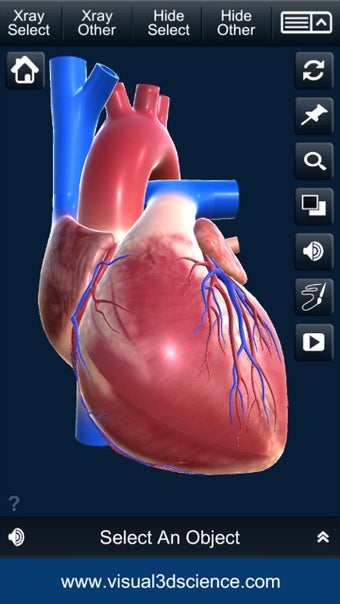

Es muy fácil de usar y muy interactiva. Puedes rotar 360°, hacer zoom y mover la cámara alrededor de un modelo 3D altamente realista.

El usuario puede seleccionar cualquier parte del corazón para ver su nombre o leer información relacionada.

Puedes seleccionar la vista de rayos X, ocultar y mostrar partes del corazón, así como ver animaciones en tiempo real, dibujar o escribir en la pantalla y compartir capturas de pantalla, pronunciación de audio para todos los términos de anatomía y más.